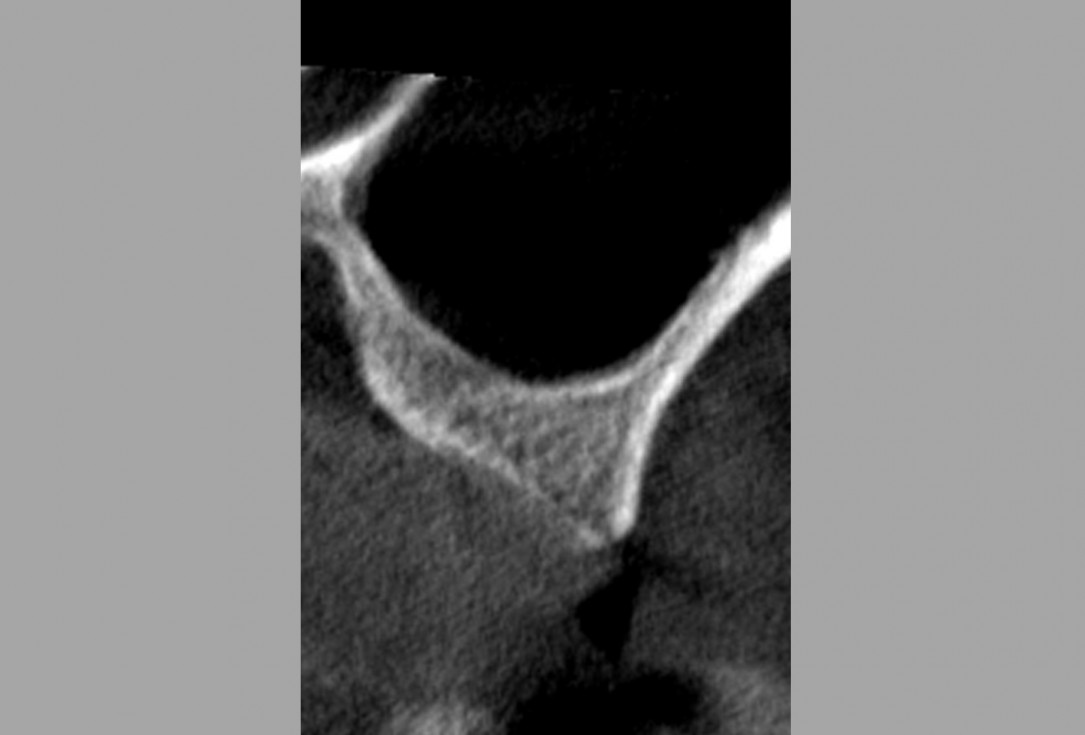

03/16 - Alveolar ridge and sinus floor CT scan before the surgery

Lateral sinus lift one-stage with cerabone® & collprotect® membrane - Dr. V. Kalenchuk